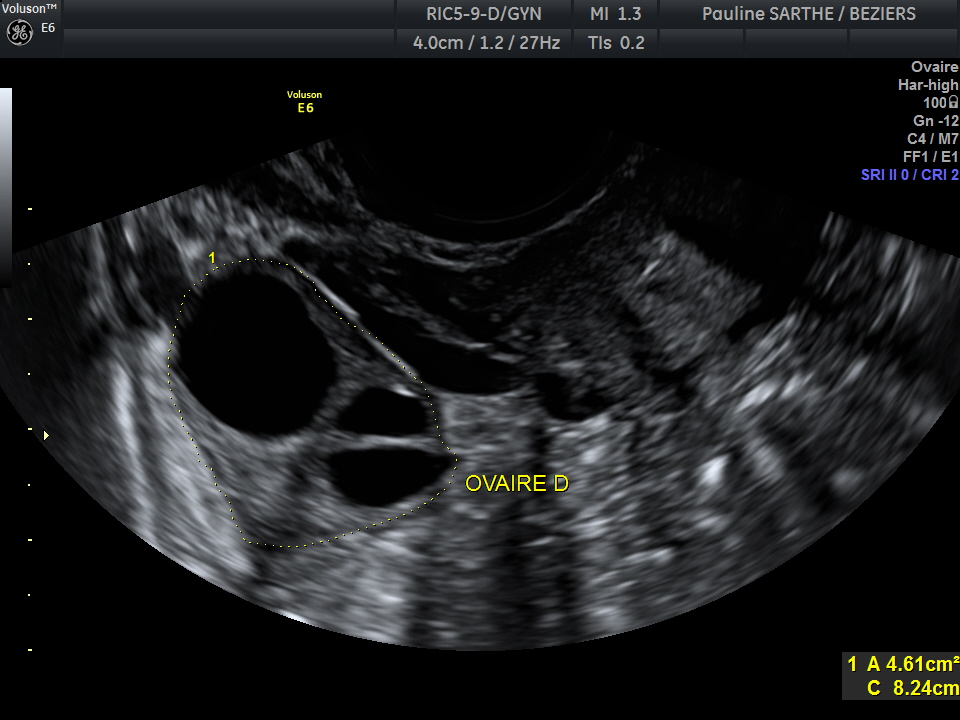

- l'échographie pelvienne

permet d'explorer les organes et tissus de la cavité pelvienne de la femme comme : la vessie, l’utérus et son col, les ovaires, les trompes de Fallope, la paroi séreuse, la paroi muqueuse, l’endomètre, le myomètre ainsi que la vascularité utérine, ovarienne et annexielle.

Elle est réalisée par voie endo-vaginale (sonde adaptée introduite dans le vagin). C'est un examen indolore.

Cet examen peut-être demandé en cas de kystes ovariens, de fibromes, de douleurs abdominales , de troubles du cycle et des règles, de vérification de dispositif intra-utérin...